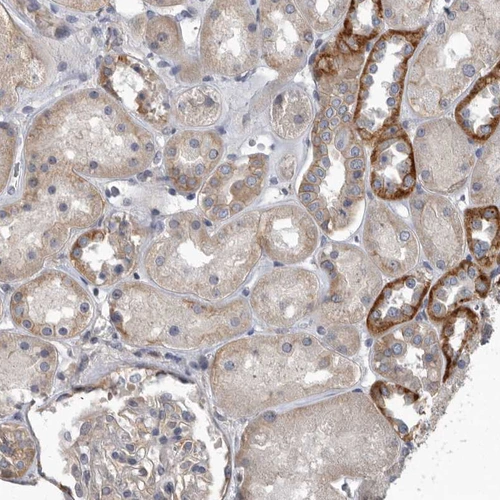

Immunohistochemical staining of human heart muscle shows strong cytoplasmic positivity in myocytes.